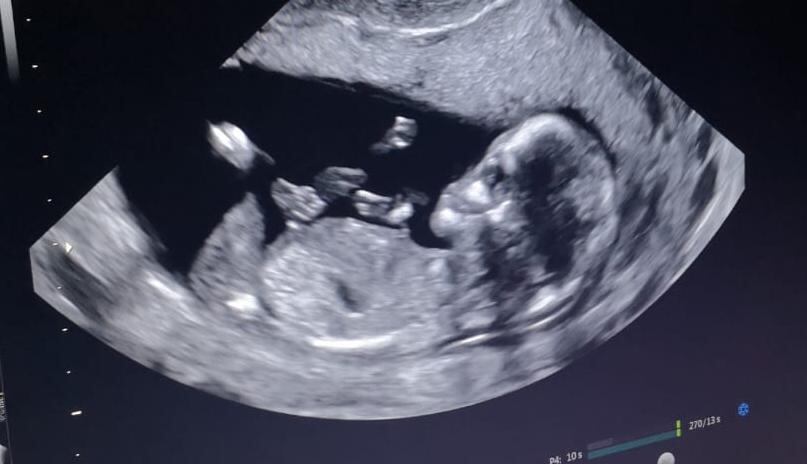

Y precisamente eso es lo que ha llegado a hacer el bebito, que lleva 17 semanas de gestación, en la familia del periodista de canal 7, pues desde hace un mes, cuando el doctor les dijo que habían pasado las semanas de peligro, todo se llenó de paz y felicidad en su hogar.